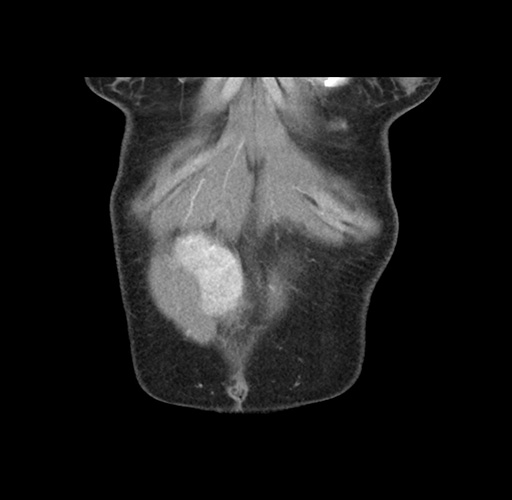

Imaging Analysis

Look through the patient's CT scan to identify any areas of concern for the necessary procedure.

Based on your CT findings, which issue(s) would give reason for "planned slowing down moment(s)" in this case?